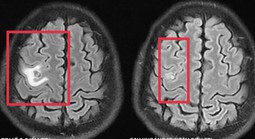

(NLĐO) - Tổn thương não do sán khiến bệnh nhân co giật, đau đầu nhẹ - triệu chứng mờ nhạt nhưng dễ bị bỏ sót.